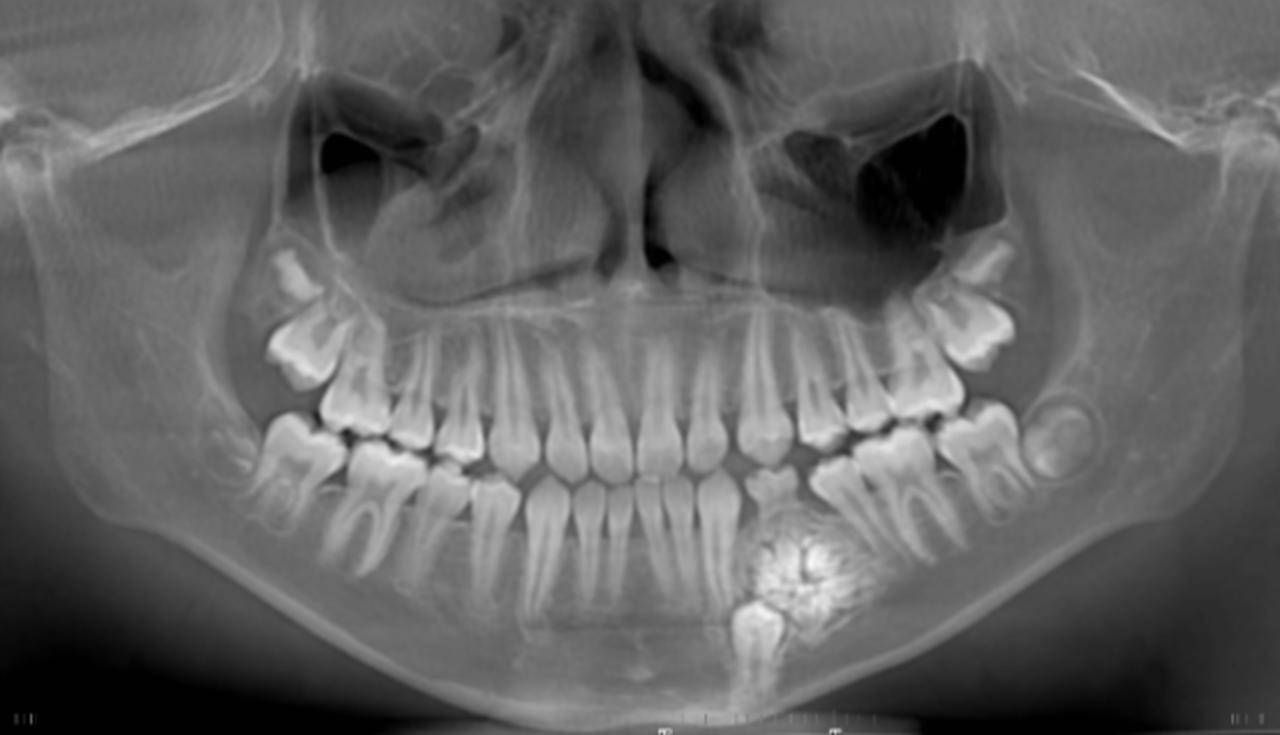

11岁的康康随着年龄的增长,逐渐出现“地包天”的面型,在父母的陪伴下来到武大口腔正畸科检查,希望进行正畸治疗。在进行口腔CT检查时,医生无意间发现其左侧下颌骨中竟然有一个巨大的球状“黑影”,遂建议其转入该院口腔外科门诊进行排查。

口腔外科门诊主任赵吉宏教授查看、检查了康康的CT结果及口腔情况后,诊断为“组合型牙瘤”,并建议康康进行手术治疗,取出牙瘤。康康和父母表示同意。

“爸妈,我害怕。”第一次做手术的康康显得有些恐惧和紧张,紧紧地攥着妈妈的手。手术中,赵吉宏主任利用无痛麻醉技术进行精准麻醉,再使用新型超声骨刀去除牙瘤表面的骨质,打开了一个直径仅1cm的微小开口,取出了直径约1.5cm的“牙瘤”,整台手术仅耗时10余分钟。康康在无痛、微创下,医生高效的完成了手术。经医生清点,牙瘤中竟有37颗大小不同、形状各异的小牙齿。